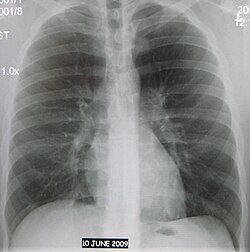

Флюорография органов грудной клетки

Флюорогра́фия органов грудной клетки — профилактический метод обследования органов грудной клетки, который проводится с использованием рентгеновского излучения, проходящего через тело человека. Из-за неравномерного поглощения рентгеновских лучей тканями, получается видимое изображение, которое проецируется на флуоресцентном экране[1]. Далее это изображение переносится на фотоплёнку относительно небольших размеров.